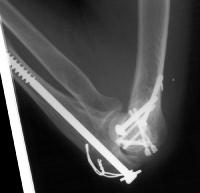

Screws were secured from the central articular component to the more proximal humeral cortices.

These provided biplanar fixation, eventually with two screws in each direction.

The lateral column was then secured with two cannulated screws.

The olecranon osteotomy was closed with a 6.5 mm lag screw and (belt and suspenders) tension band technique.

Anatomic reduction.